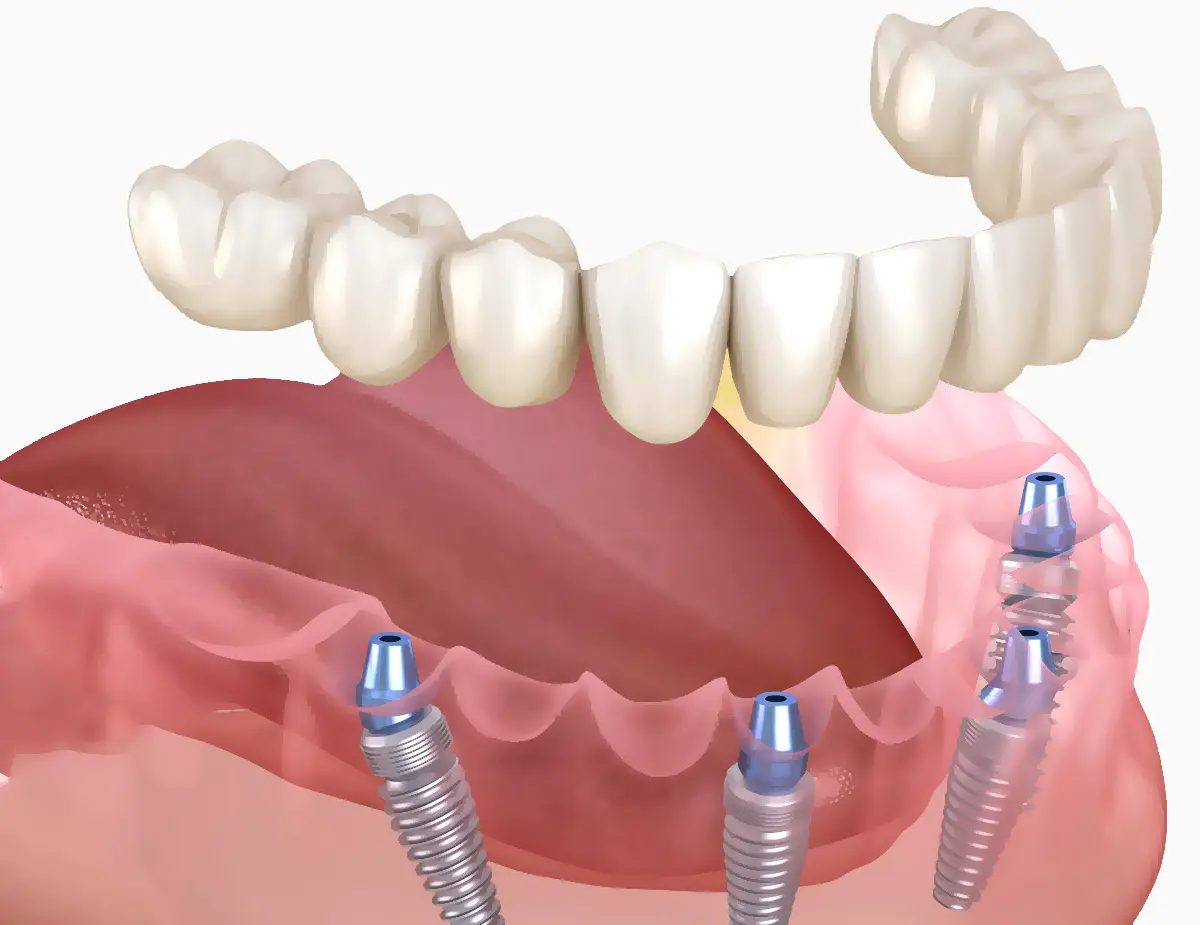

Protetika na implantatima

Moguće opcije za zamjenu izgubljenih zuba uključuju dentalne mostove, dentalne implantate te parcijalne i totalne proteze. Svaka opcija ima svoje prednosti, a stomatolog će vam pomoći odabrati najbolju opciju ovisno o vašem individualnom stanju i potrebama.

Zubni implantati osmišljeni su kao trajno rješenje za nadomještanje zuba koji nedostaju. Uz pravilnu njegu i održavanje, mogu trajati cijeli život. Naša klinika koristi vrhunske implantate najviše kvalitete kako bi osigurala dugotrajnost i uspjeh implantološkog tretmana.